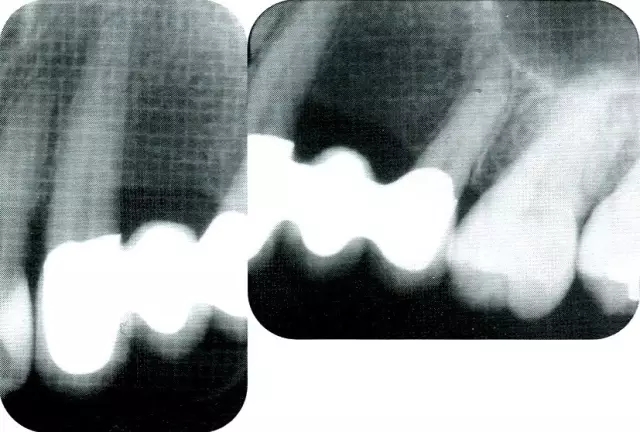

640.webp (1).jpg

▲圖7-2  術(shù)前x片。確認存在垂直性深骨缺損。